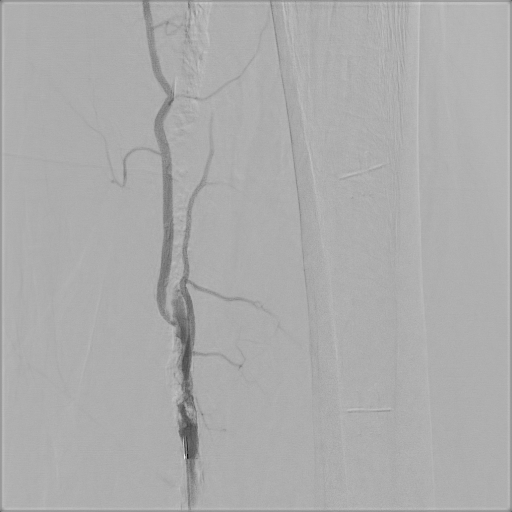

Owning to multiple stenosis and total occlusion, terumo wire cannot pass through the lesion. we ever use Connect wire, V-18 wire and even shift to Astato for calcified lesion with the assist of CXI. After several times attempt of antegrade wiring, the V-18 wire finally pentrate thrthrough the calcified lesion and advanced to distal popliteal artery. Finally the V-18 wire pass the lesion and balloon angioplasty was performed. Diffuse dissection with TIMI II flow was discovered after balloon angioplasty, thus we deployed Supera stent at SFA.Final angiogram showed acceptable result.

Despite multiple calcified lesion and totally occluded vessel length longer than 200mm, with the guidance of calcification and distal true lumen angiogram, we use crossover-antegrade approach to pass through the lesion with successful balloon angioplasty and stenting. Final result was TIMI III flow of distal limb and the patient's symptoms subsided.